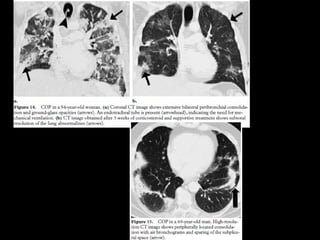

Aguda/subaguda COP • Ex BOOP •Asociada a : colágeno, infecciones, EII, radiación, toxicidad, transplante órganos Criptogénica: idiopática 55 h=m 4- 6 semanas con síntomas de gripe Buen pronóstico

COP CT • Consolidacionesparcheadas • Broncograma aéreo Signo halo inverso • Vidrio esmerilado periférico o peribroncovascular • Crazy paving • LI • Nódulos, cavitarse • Puede simular neumonía • Reticulación subpleural • Derrame pleural

Bilateral or unilateralpatchy alveolar airspace consolidation is revealed, often subpleural and peribronchial in location and mainly in the lower zones. Generally, the infiltrates gradually enlarge from their original size or new infiltrates appear. Consolidation is often nonsegmental and varies from 2 to 6 cm in diameter. Cavitary BOOP that mimics tuberculosis and cavitating opacity after lung transplantation has been reported. An air bronchogram may be present. Nodules 3-5 mm in diameter are seen in approximately one half of patients; nodules may be migratory. Basal linear opacities are linked to a poorer prognosis. Unilateral focal or lobar consolidation occurs in 5-31% of patients. Miliary pattern is rare. Pleural thickening occurs but pleural effusions are rare.